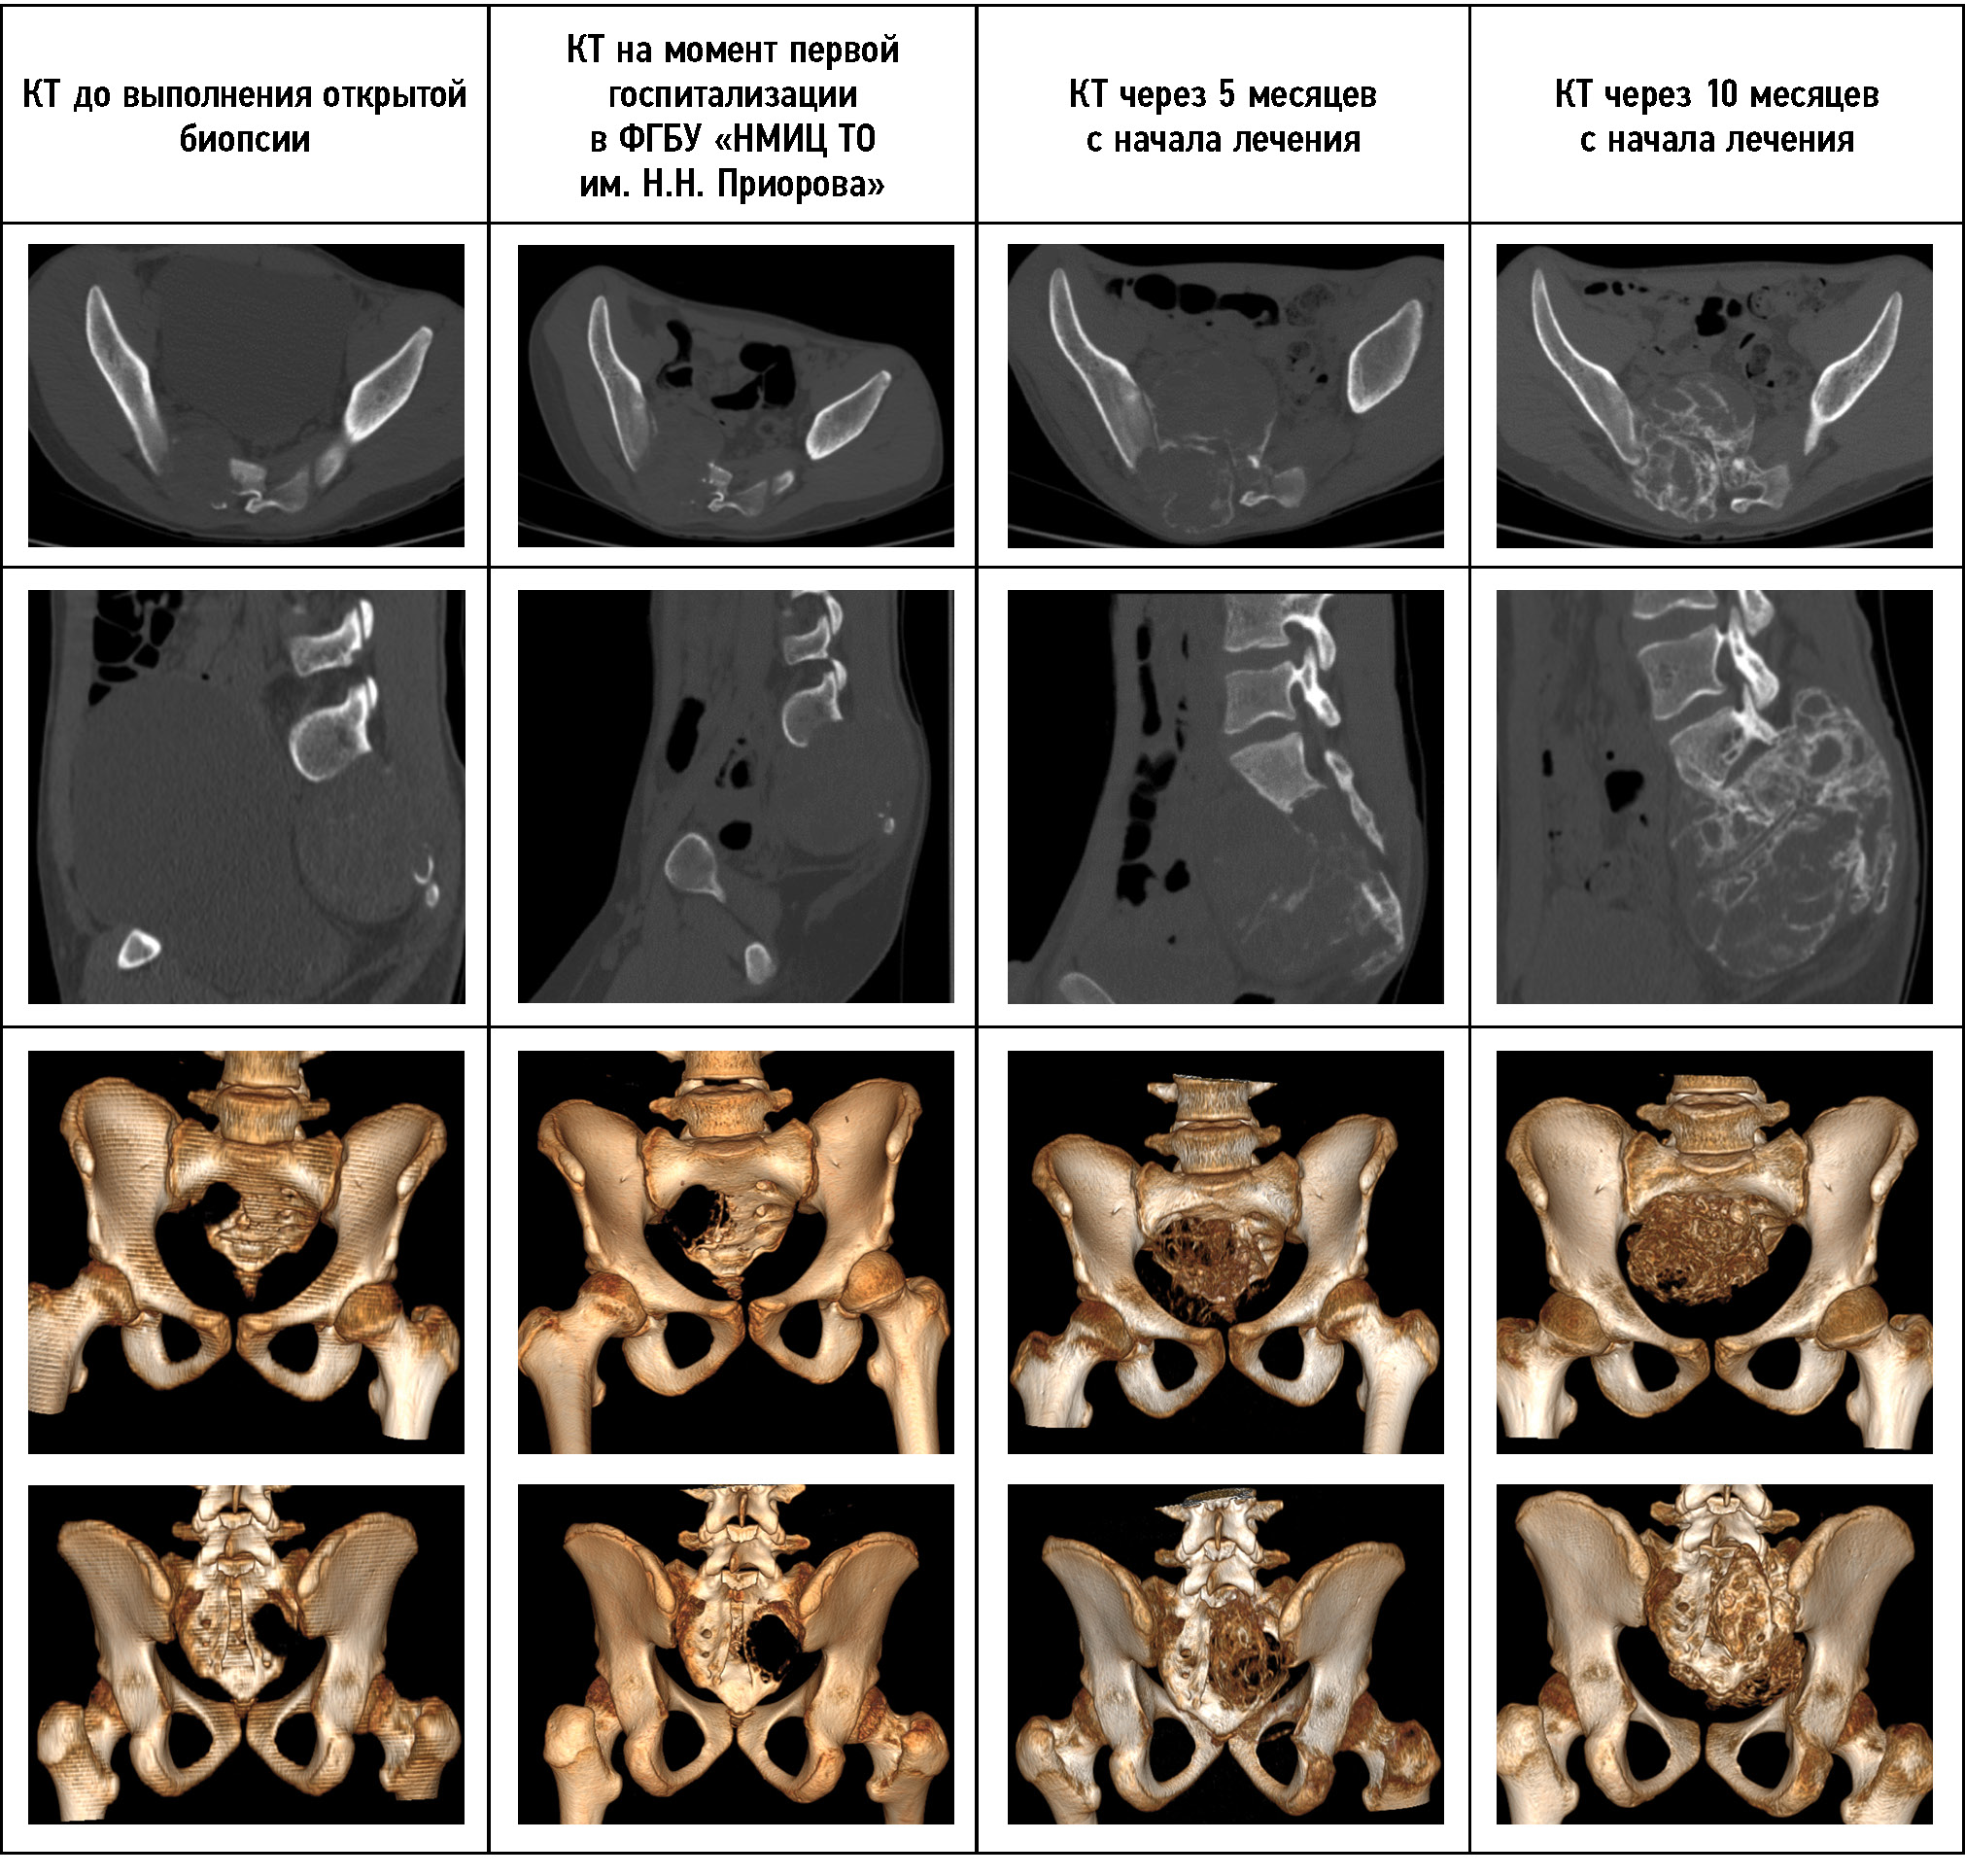

На момент начала лечения возраст пациента составлял 12 лет. С сентября 2014 года предъявлял жалобы на боль в крестцовой области, хромоту на правую нижнюю конечность. Срок жалоб — 5 месяцев. По месту жительства выполнены рентгенограмма костей таза, МРТ, КТ костей таза, диагностирован патологический очаг в крестцовой области на уровне S1-2. Была выполнена открытая биопсия с экскохлеацией патологического очага. По данным гистологического исследования диагностирована аневризмальная киста S1-2. Пациент направлен в ФГБУ «НМИЦ ТО им. Н.Н. Приорова». При первой госпитализации по данным КТ и МРТ (рис. 6, 7) можно наблюдать патологический очаг S1-2 позвонков с чёткими уровнями жидкости, компрессией невральных структур и частичным окостенением оболочек опухоли. При пересмотре гистологических препаратов в ФГБУ «НМИЦ ТО им. Н.Н. Приорова» диагноз АКК подтверждён. С декабря 2014 г. начато пункционное лечение. Во время первой пункции внутрикистное давление составило 415 мм вод. ст. В первые 4 года пациент госпитализировался в 11-е отделение ФГБУ «НМИЦ ТО им. Н.Н. Приорова» один раз в 2–3 месяца. Следующие 3 года — один раз в 4–5 месяцев. При динамическом контроле отмечалась положительная динамика. Жалобы пациента регрессировали спустя 4 месяца с момента начала лечения. На восьмом году наблюдения отмечена остаточная резидуальная полость опухоли в задних отделах крестца без клинических проявлений. При пункции выявлена низкая активность кисты, давление минимальное. Учитывая данные КТ, пациенту выполнена открытая операция в объёме резекции патологической ткани, эвакуации геморрагического компонента опухоли с одномоментной костной пластикой аллотрансплантатами. Операция выполнялась под общим наркозом, её длительность составила 36 мин, объём кровопотери — 100 мл. В отдалённом периоде продолженный рост не выявлен в течение двух лет. Данные изменения измерений опухоли указаны в табл. 1.

Рис. 7. КТ-динамика лечения пациента 3. На КТ через 8 лет от начала лечения определяется формирование резидуальной полости.

Fig. 7. The CT-dynamics of the patient’s treatment № 3. After 8 years of treatment, a residual cavity was determined on CT.